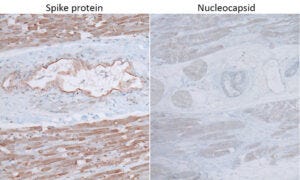

7. Injected persons express only the spike protein, which implicates the vaccine

Here, we see immunohistochemistry applied to heart muscle tissue from an injected person. Staining for the presence of spike protein causes strong brown pigment deposition. In contrast, only very weak, non-specific staining is observed with the antibody that recognizes the nucleocapsid protein. The absence of nucleocapsid indicates that the expression of the spike protein must be attributed ot the vaccine rather than an infection with SARS-CoV-2.

We will see shortly that the strong expression of spike protein in heart muscle after vaccination correlates with significant inflammation and tissue destruction.

8. Expression of spike protein within the walls of small blood vessels

We see spike protein expression in arterioles (small arteries; left) as well as in venules (small veins) and capillaries (right). Expression is most prominent in the innermost cell layer, the endothelium. This makes the endothelial cells “sitting ducks” for an attack by the immune system.